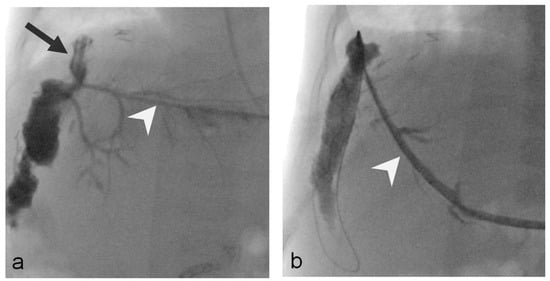

- Uller, W.; Wohlgemuth, W.A.; Hammer, S.; Knoppke, B.; Goessmann, H.; Loss, M.; Schlitt, H.J.; Stroszczynski, C.; Zorger, N.; Heiss, P. Percutaneous treatment of biliary complications in pediatric patients after liver transplantation. Rofo 2014, 186, 1127–1133. [Google Scholar] [CrossRef]